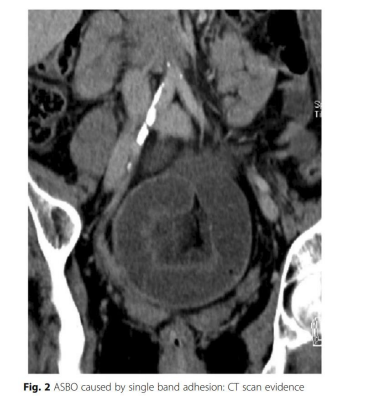

2.5. Chẩn đoán bằng CT bụng

- Chẩn đoán tắc ruột non + 90% các trường hợp nghẹt ruột cần PT

- Giá trị chẩn đoán càng cao khi sử dụng chất cản quang tan trong nước

- Giúp phân biệt tắc ruột hoàn toàn do đó tạo điều kiện cho quyết định điều trị nội khoa so với chỉ định mổ cấp cứu ngay

- Giúp xác định vị trí tắc (hỗng tràng hoặc khung chậu)

Dấu hiệu quai ruột đóng, thiếu máu ruột và dịch tự do bằng phẫu thuật

- Mặc dù dính ruột không thể nhìn thấy trực tiếp trên CT, nhưng chụp CT có thể giúp chẩn đoán phân biệt các nguyên nhân tắc ruột khác

→ CT được coi là phương tiện chẩn đoán thích hợp nếu có bất kỳ nghi ngờ nào về chẩn đoán tắc ruột do dính sau mổ và để đánh giá sự cần thiết của can thiệp PT